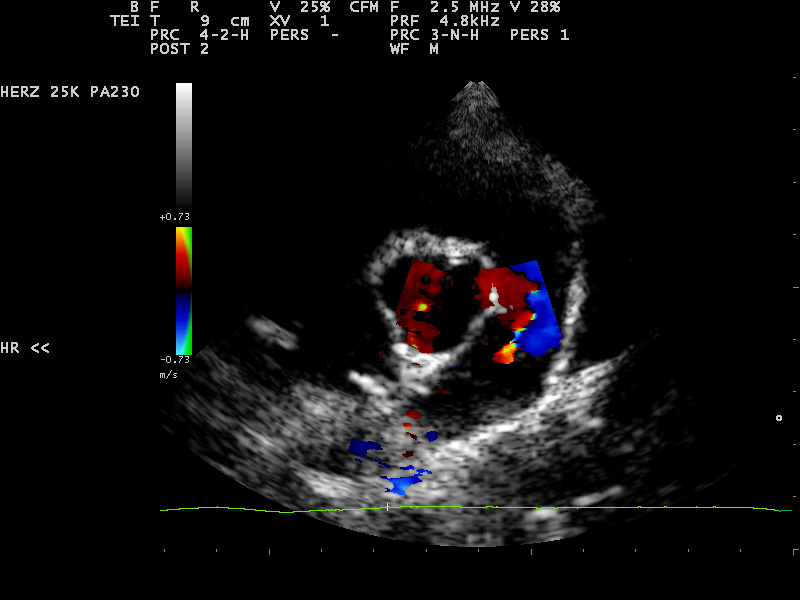

Zunächst wurde von den Kollegen - aufgrund des zeitlichen Zusammenhangs - eine Impfreaktion vermutet, woraufhin Elliot starke Schmerzmittel bekam. Allerdings besserte sich seine Lahmheit weder durch Schmerzmittel noch durch Kortison wesentlich. Da man äußerlich nichts feststellen konnte, wurde eine erste Röntgenuntersuchung des Rumpfes durchgeführt, bei der aber die Ursache leider nicht gefunden wurde. Als auch nach dieser weder Fieber noch Lahmheit verschwanden, wurde der Hund zur Spezialdiagnostik überwiesen. Es sollte nun bei uns in der Klinik erneut geröntgt und eventuell eine Computertomographie durchgeführt werden. Bei der Eingangsuntersuchung vor der notwendigen Narkose wurde ein kontinuierliches Herzgeräusch festgestellt. Dieses konnte nur unter dem linken Schulterblatt in Höhe des 2.-3. Zwischenrippenraumes auskultiert werden. An dieser Stelle war es aber sehr laut (Grad 5 von 6) und gut hörbar. Der untersuchende Kardiologe stellte einen klinisch relevanten PDA (Ductus arteriosus botalli persistens) fest, der sich schon in einem behandlungswürdigen Stadium befand. Daher war an eine Narkose zur Abklärung der Lahmheit an diesem Tage nicht zu denken.

Erfreulicherweise verschwindet die Erkrankung mit Ende des Knochenwachstums. Für Elliot zunächst aber das kleinere Problem. Ein PDA, wie er im Herzen von Elliot festgestellt wurde, verläuft für fast 2/3 der Welpen im ersten Lebensjahr tödlich. Daher muss dieser verschlossen werden. Bei dem PDA handelt es sich um ein Blutgefäß, welches sich nach der Geburt nicht ordnungsgemäß verschlossen hat. Deshalb fließt Blut auch nach der Geburt an der Lunge vorbei zurück in das linke Herz, welches sich daraufhin stark vergrößert.